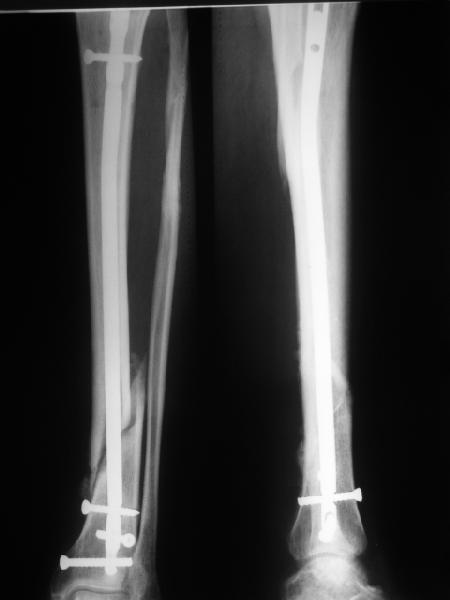

Стержень с большим диаметром и подлиннее?

С ходу не могу понять, почему неправильно фиксирован перелом.

Внизу стержень всего один статический винт держит?

Вальгус, стержень в дистальный отломок введен не на оптимальную длину. Такой диастаз будет долго заполняться, что чревато переломом стержня по ближайшему отверстию.

Вальгус сам по себе небольшой. Имеется промежуточный отломок, который не притянулся, так как отломки до конца не растянули. Сейчас наверное стоит подождать 2-3 мес. и посмотреть как пойдет срастание.

На снимке сохранен небольшой вальгус, но имеется нормальная аппозиция медиального кортикального слоя и поэтому трудно согласится что здесь имеется неправильно фиксированный перелом. Для идеального сопоставления таких косых переломов надо открывать фокус травмы, но тогда меняется философия фиксации.

Аховых проблем с синтезом нет, да гвоздь коротковат, вальгус небольшой, но это не повод для реостесинтеза. Динамизация тоже рановато, т.к она потребует удаления всех проксимальных винтов. Оставьте в покое еще на 1-1,5. А что думает оперирующий хирург? Почему больной наблюдается не у него?

Честно говоря не знаю, какой вальгус допустим, но, учитывая то, что он виден "на глаз", учитывая возраст, проблемы в последующем с коленом очень вероятны. Наверное лучше переделать.

Вы бы стали оперировать или рекомендовали бы своему родственнику оперироваться из-за 2 градусов?

Все наши сомнения связаны с тем, что этих незначительных погрешностей (небольшой вальгус, неглубоко пробит гвоздь, мало запирающих винтов в

дистальном отломке) не одна, а несколько, и вместе они могут значительно осложнить дальнейшую жизнь пациенту. В нашей практике были подобные случаи, при которых после разрешения полной нагрузки либо начинала увеличиваться деформация, либо происходил перелом гвоздя по ближайшему отверстию. Кроме того, при диафизарных переломах, имея в арсенале надежный фиксатор, нет никакой необходимости вынуждать пациента ограничивать нагрузку на ногу в течении 2-3 месяцев.